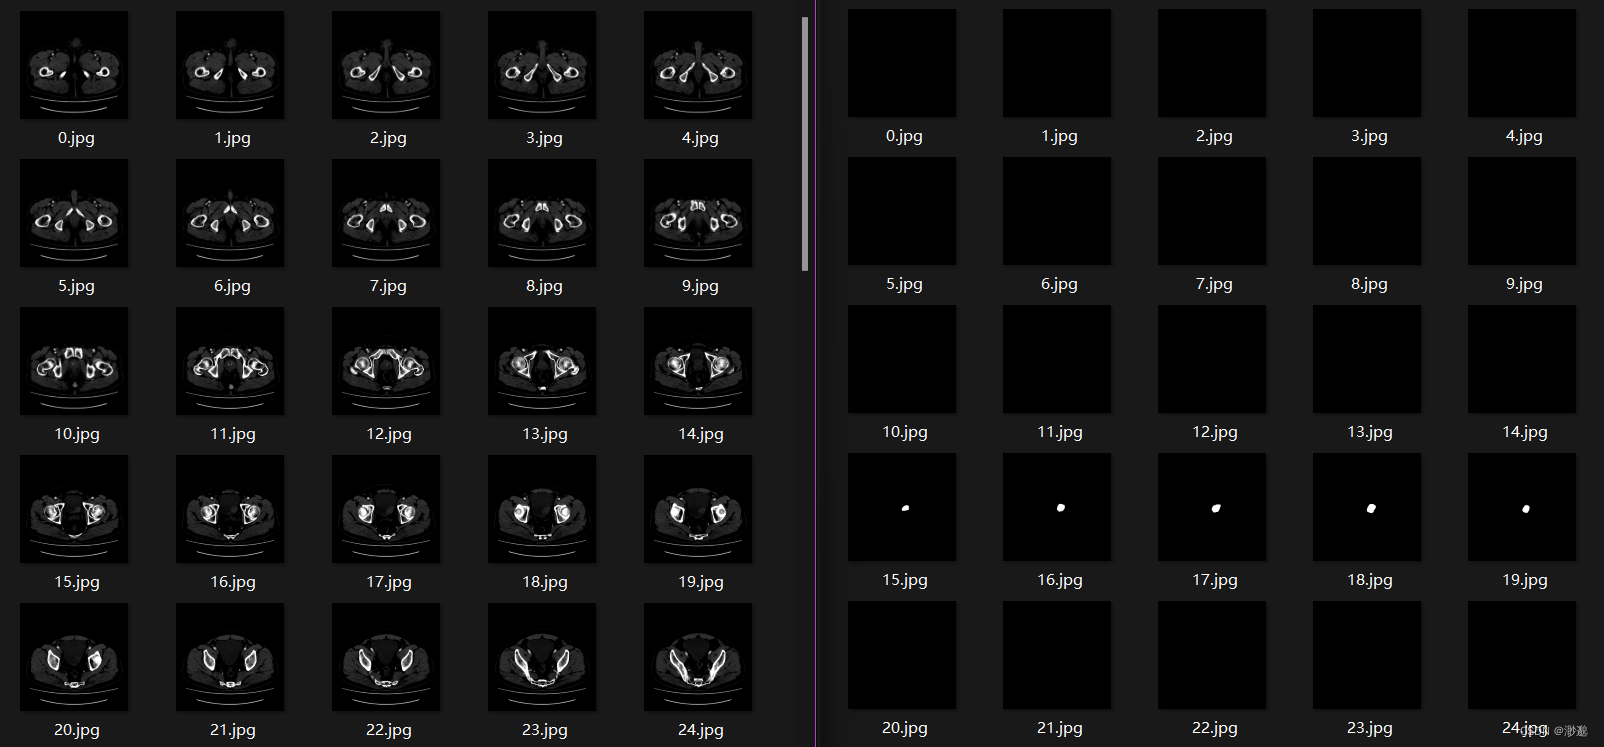

接下来以DICOM原始影像 nii勾画文件为例,为您演示原始影像与勾画文件的转JPG过程。

成功将dicom与mask都转换为了jpg

为了更好的查看mask在原始影像的位置,我们需要将mask覆盖到原始影像上。

执行完毕后将得到以下图像:左侧为原始影像,右侧为勾画覆盖影像。